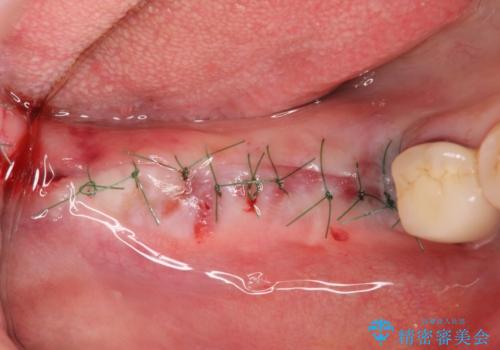

インプラントの埋入には十分な骨量が必要ですが、虫食い状に骨が足りなかった為インプラントの埋入と同時に骨の増成を行いました。

インプラントを埋入する手術と同時に骨の増成を行う場合と、埋入前に骨の造成だけを行う場合があります。